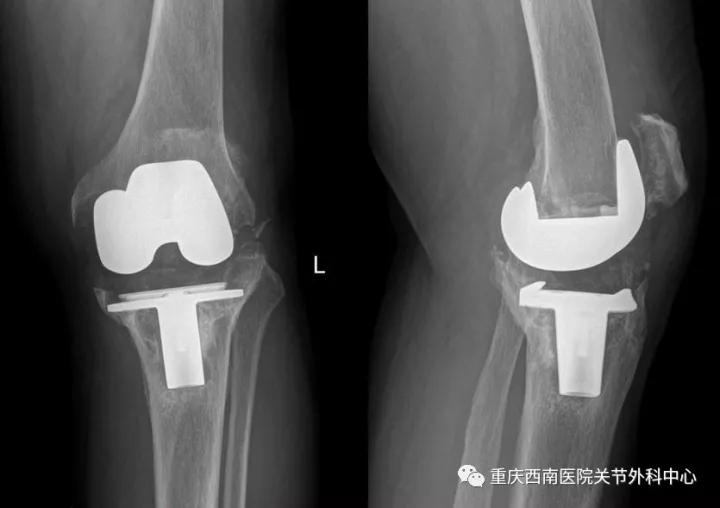

术前X光片